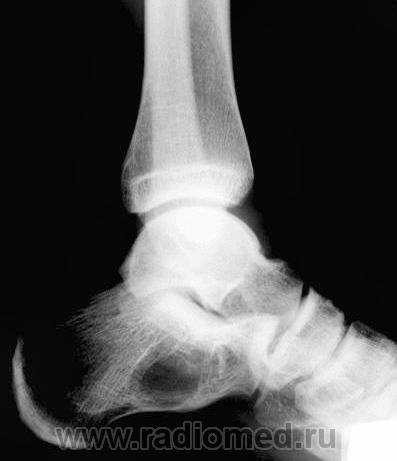

жалобы на незначительные боли в области левой пятки. несколко меяцев назад была травма,после которой полявиась припухлость в области пятки.К врачу не обращался. После мед осмотра в школе направлен на рентгенографию.

Навскидку - костная киста.

киста пяточной кости и вальгусная деформация голеностопного сустава

1- псевдокиста пяточной кости, данная локализация характерная, но клинику она обычно не даёт а если и дает то редко, я уже выкладывал случай:

2-остеомиелит, возможно посттравматический;

3- менее вероятно доброкачестванная новообразование;

Мы довольно часто встречаемся с такой патологией - костная киста, при проведении экспертизы годности к военной службе, при рентгенометрии "продольного плоскостопия", и довольно часто это патологическое состояние бывает с одной стороны.